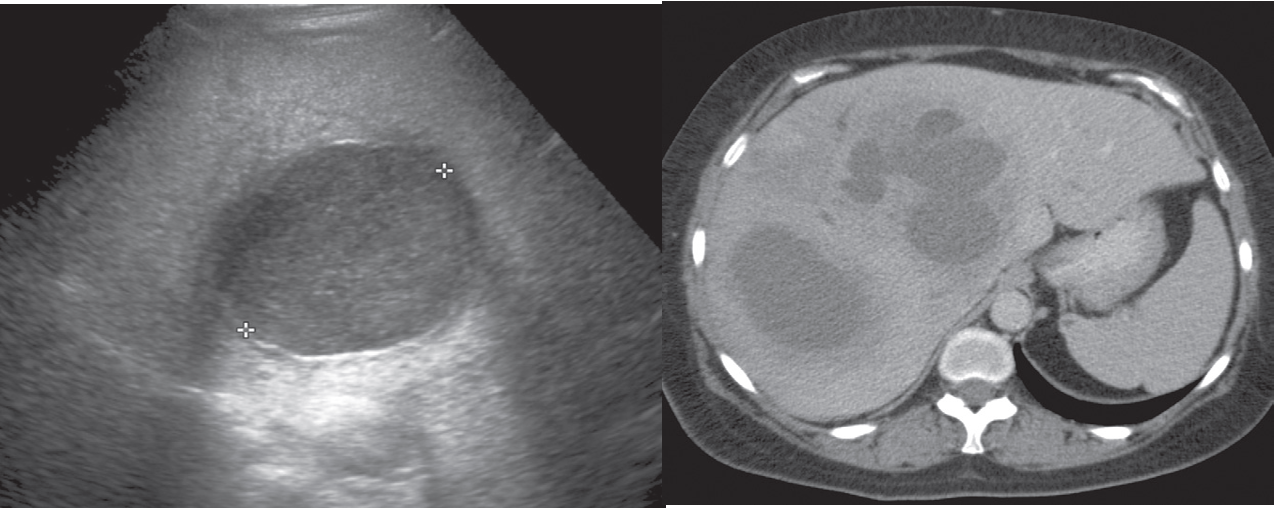

Hepatic abscesses tend to have fluid centres, with walls that are thicker, more irregular and more obvious than those of simple cysts.

Aspiration and drainage are invariably undertaken in any case of suspected abscess and are *convenie**ntly *performed under ultrasound guidance.

Liver abscess. (a) Ultrasound scan showing an area of mixed echogenicity in the liver. (b) CT in another patient showing multifocal areas of low attenuation.